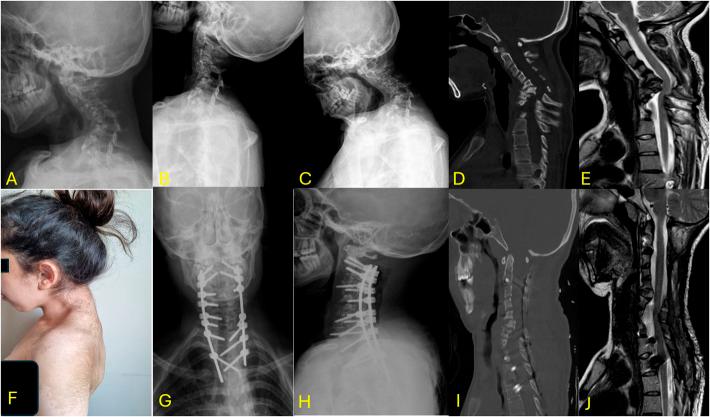

在伴有神经纤维瘤病1型(NF1)的儿童颈椎后凸畸形中,采用颈椎椎弓根螺钉固定而非侧块固定进行一期矫正的手术结果:一项至少随访2年的回顾性研究

Surgical Outcomes of Single-Stage Correction Using Cervical Pedicle Screw Fixation Rather Than Lateral Mass Fixation in NF1-Associated Pediatric Cervical Kyphosis: A Retrospective Study with a Minimum 2-Year Follow-Up.

Neurofibromatosis type 1 (NF-1) can cause severe kyphosis in the cervical vertebrae. There is no consensus on the optimal surgical treatment for this rare condition, although long-segment fixation and combined approaches are generally preferred. To our knowledge, this study is the first to report the clinical outcomes of patients with NF-related cervical kyphosis who underwent stand-alone posterior pedicle fixation surgery.

METHODS

The outcomes of 14 patients who underwent surgery using the pedicle screw were retrospectively examined between 2015 and 2022. Only patients with at least 2 years of follow-up were included. For each patient, the following parameters were recorded and evaluated at 1 month postoperatively and at the end of the follow-up period: cervical lordosis (CL), local kyphosis angle (LKA), T1 slope, cervical sagittal vertical axis, visual analog score for neck pain, modified Japanese Orthopedic Association score, and Neck Disability Index. Complications, surgical duration, blood loss, levels of instrumentation, and length of hospital stay were also recorded.

RESULTS

In terms of radiographic parameters, all patients achieved lordosis, with the cervical LKA improving from an average of 76.7° preoperatively to an average of 20.4° in the early postoperative period. At the 2-year follow-up, the postoperative CL significantly improved compared with preoperative values (p < 0.001) with only approximately 4° correction loss. Moreover, by the end of the follow-up, all postoperative symptoms showed improvement compared with the preoperative symptoms. The average surgical duration was 211.86 ± 49.83 min. During the follow-up, junctional kyphosis was observed in 4 patients all of whom required revision surgery. C5 palsy was detected in 3 patients. Infection-related complications occurred in 6 patients, with wound infection in only 1 patient.

CONCLUSION

Cervical pedicle screw fixation is an effective treatment for NF-1-related cervical kyphosis. Although this technique is considered difficult and dangerous to apply by several spine surgeons, it exerts a positive effect on clinical improvement and provides optimal correction.

1型神经纤维瘤病(NF-1)可导致严重的颈椎后凸。对于这种罕见病症的最佳手术治疗方法尚无共识,尽管通常更倾向于采用长节段固定和联合手术方式。据我们所知,本研究是首例报告接受单纯后路椎弓根固定手术的NF相关颈椎后凸患者的临床结局。

方法

回顾性分析2015年至2022年间14例行椎弓根螺钉手术患者的结局。仅纳入随访至少2年的患者。对每位患者,在术后1个月和随访期末记录并评估以下参数:颈椎前凸(CL)、局部后凸角(LKA)、T1斜率、颈椎矢状垂直轴、颈部疼痛视觉模拟评分、改良日本骨科协会评分和颈部功能障碍指数。还记录并发症、手术时长、失血量、内固定节段数和住院时间。

结果

在影像学参数方面,所有患者均实现了前凸,颈椎LKA从术前平均76.7°改善至术后早期平均20.4°。在2年随访时,术后CL与术前值相比显著改善(p < 0.001),仅约4°的矫正丢失。此外,到随访结束时,所有术后症状与术前症状相比均有改善。平均手术时长为211.86 ± 49.83分钟。随访期间,4例患者出现交界性后凸,均需翻修手术。3例患者检测到C5麻痹。6例患者发生感染相关并发症,仅1例患者出现伤口感染。

结论

颈椎椎弓根螺钉固定是治疗NF-1相关颈椎后凸的有效方法。尽管该技术被一些脊柱外科医生认为应用困难且危险,但它对临床改善有积极作用并提供了最佳矫正。